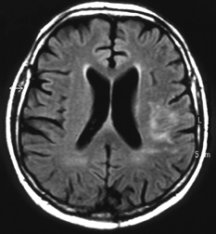

In a small pilot study of people with stroke in Germany, 20 patients treated with EPO within 7 hours of stroke later had fewer physical, speech, and memory problems and needed less day-to-day assistance than did 20 who didn’t get the hormone. People treated with EPO also tended to have smaller areas of damaged brain tissue, as measured by brain scans a month after their stroke.

People who have had the most-severe strokes seem to benefit most from treatment with EPO, reports Hannelore Ehrenreich of the Max-Planck Institute for Experimental Medicine in Göttingen, Germany. She and her colleagues published their findings in the August Molecular Medicine. The German team is now developing a trial of about 500 patients at several medical centers.

At least at this early stage in the evaluation, the benefits from EPO for stroke appear to be at least equivalent to that of tPA, Easton says. However, unlike tPA, which poses life-threatening risks of hemorrhage and thus can only be given in hospitals, EPO may be safe enough for potential stroke patients to get the drug on their way to the hospital, he adds. Since the two drugs work in different ways, physicians might also combine them.